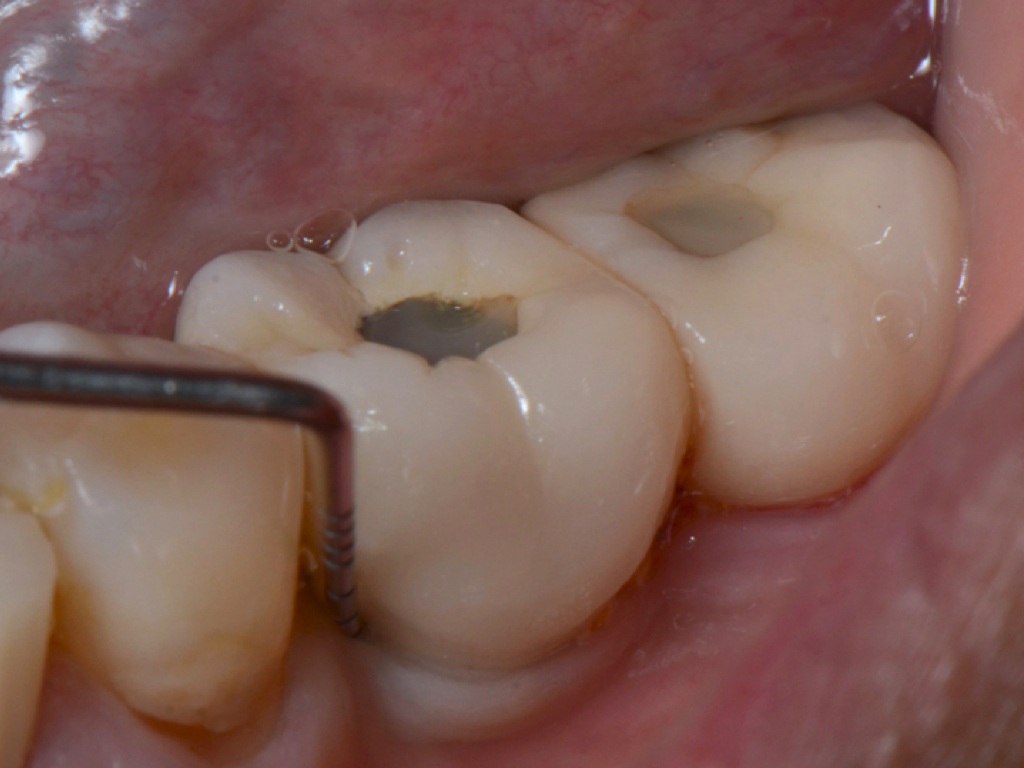

Similar to natural teeth, measurements of PPD and BoP before and after treatment are clinical parameters often used to determine the health of dental implants (Figure 4 and Figure 5). However, due to the difference between periodontal and peri-implant anatomy, concerns have been raised about the use of probes in peri-implant tissues around dental implants. These include the risk of peri-implant tissue damage,17,18 risk of damage to the implant surface by the metallic probe,19-21 risk of bacteria inoculation,22-27 and risk of galvanic corrosion resulting from contact between two dissimilar metals.21,28-30 These risks are discussed in the following sections.

Probing the sulcular depth around a dental implant is an important clinical exercise to assess implant health and stability. Longitudinal measurement of probing depth helps monitor the integrity of the peri-implant tissues. An increase in the probing depth usually indicates loss of alveolar bone support. Increasing probing depth over time in the presence of BoP and gingival exudate are criteria to diagnose peri-implant disease.33 Increased probing depth accompanied by BoP without concomitant bone loss has been defined as peri-implant mucositis.34 When these signs are present with radiographic (or sounding) evidence of bone loss, the disease has been defined as peri-implantitis.34

Probing is useful to determine the presence of biological complications at the buccal and lingual sites of implants, which cannot be evaluated on a radiograph (Figure 6 through Figure 8). Because of the absence of a periodontal ligament, bone loss on the buccal and lingual aspects of an implant indicates loss of support for the implant and may be a sign of additional circumferential bone loss around the implant.35

Due to the various aforementioned factors that can affect probing depth around an implant, a probing depth of 4 mm to 5 mm around an implant may not be as critical a diagnostic parameter as it would be around natural teeth (Figure 9 and Figure 10). However, probing depth accompanied by BoP becomes a significant concern around an implant. Therefore, while incidental measurement may not be indicative of the health status of the peri-implant tissue, probing at various time intervals enables assessment of health status and disease progression.

Fig 4. Increased probing depth around an implant with BoP indicates presence of peri-implant disease and the need for taking a radiograph.

Figure 4